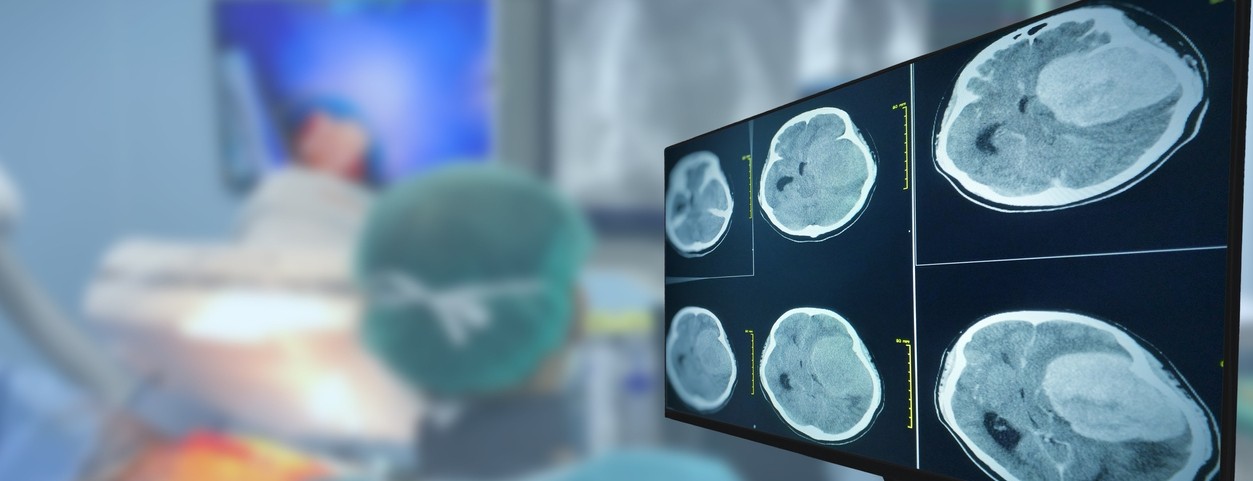

Featured photo at top of a CT brain scan. Photo/Tonpor Kasa/iStock.